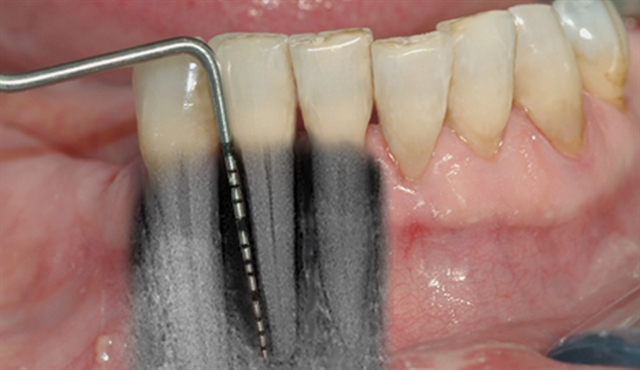

En undersøkelse med lommeregistrering avdekker likevel et omfattende bentap ved den ene tannen.